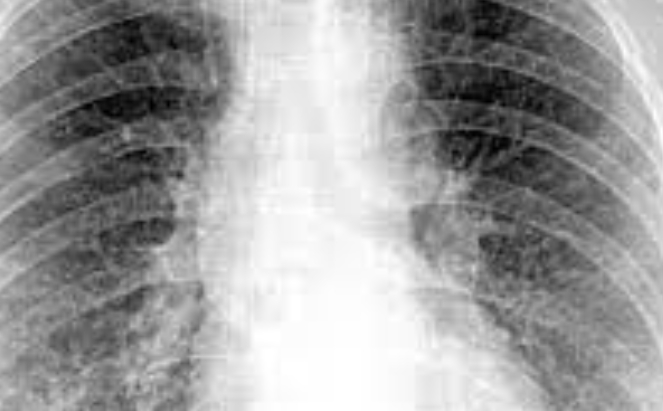

흉부 X-레이 및 CT 스캔

흉부 X-레이와 CT 스캔은 폐 조직의 섬유화 정도와 패턴을 확인하기 위해 사용됩니다.